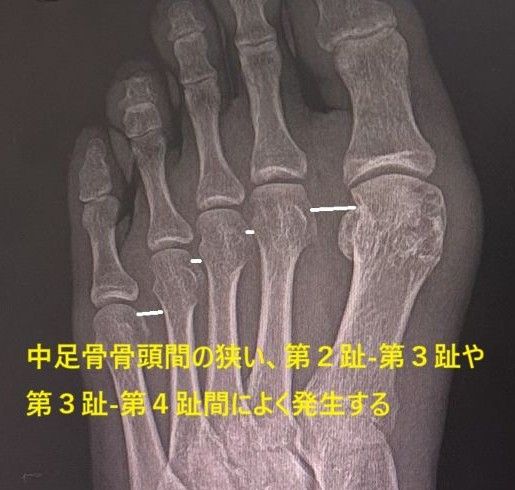

ハイヒールの使用や窮屈な靴での長時間の作業やスポーツ活動などで足指が過度に伸ばされたり、締め付けられて総底側趾神経が圧迫されて起こります。時に、

ガングリオンなどの腫瘍によって生じた症例を経験します。女性に多く、好発部位は第2趾‐第3趾、第3趾‐第4趾間です。